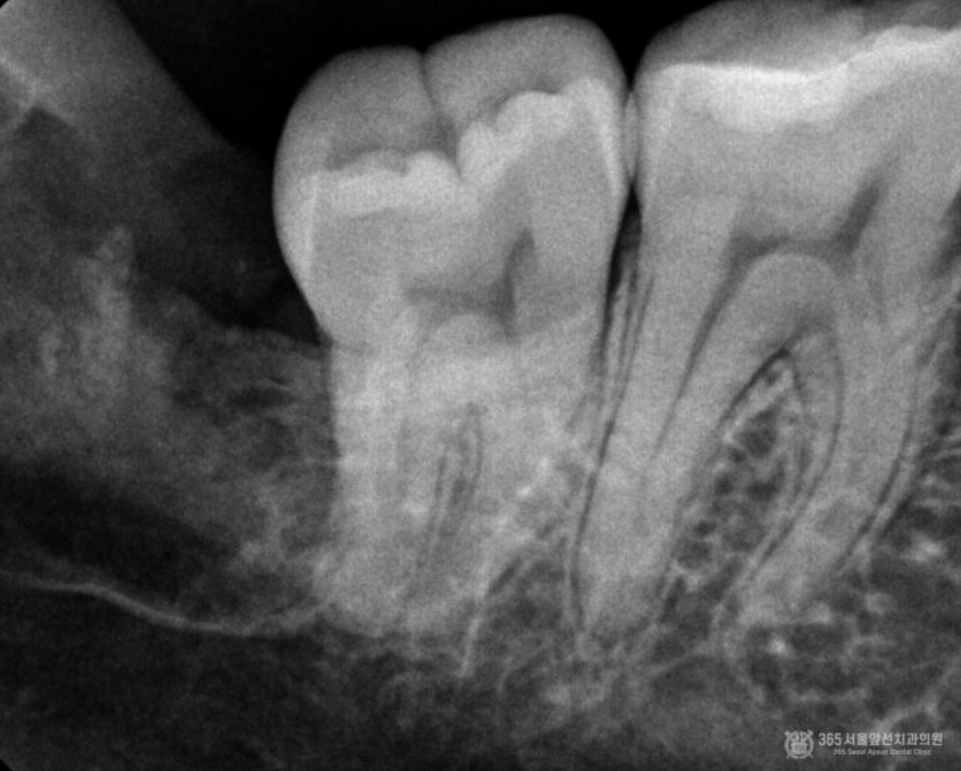

촬영일시 : 2024.09.06. 대략 15분 정도 지나서 발치를 완료한 후 남은 치아조각이 있는지 확인차 촬영한 작은 엑스레이 사진입니다. 남은 치아 조각 없이 깨끗하고 안전하게 발치된 모습을 볼 수 있습니다 ㅎㅎ 촬영일시 : 2024.09.06. 전체 엑스레이 사진입니다. 깔끔하게 발치된 모습을 볼 수 있습니다 ㅎㅎ 전체 엑스레이 사진입니다. 깔끔하게 발치된 모습을 볼 수 있습니다 ㅎㅎ 난이도 높은 매복 사랑니 발치 또한 자신있게 치료하는 주안역사랑니치과 365서울앞선치과였습니다 ㅎㅎ [ 치료기간: 2024년 9월 6일 ] ※ 365서울앞선치과의원의 모든 포스팅은 각 진료과 의료진이 직접 작성합니다. 365서울앞선치과의원 블로그의 임상 케이스 게시물은 환자분께 의학적으로 정확하고 상세한 정보를 드리기 위해 각 진료과 의료진이 직접 작성하며, 모든 증례 사진은 본원 의료진이 직접 시술한 증례를 촬영한 것으로, 의료법 제23조, 제56조에 의거하며 환자분의 동의를 얻어 포스팅에 사용하였습니다. 또한 해당 케이스는 본 환자분의 치료 결과이며, 환자 상태에 따라 치료의 결과는 달라질 수 있습니다. |